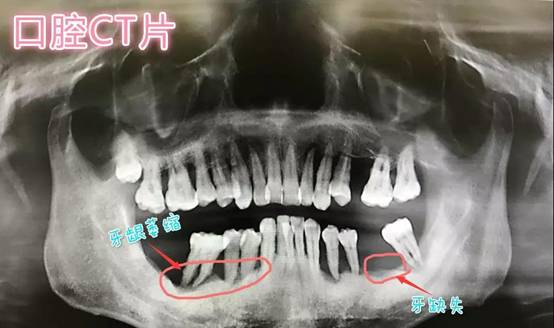

给我种植牙的是贝恩的曾小法院长,通过CBCT的检查,可以从图片中看见我下半口已经多颗牙缺失,邻牙松动、牙龈萎缩,并且曾院长说我还有牙周病。其实我从二十几岁就开始缺牙了,但是没重视起来也没修复。曾院长告诉我:久经缺牙,导致邻牙松动、牙缝增大、牙龈萎缩,再加上没有护牙意识,患上牙周病。影响吃食是常事,口腔有异味和经常牙龈肿胀、溃疡、出血才叫人痛苦不堪。